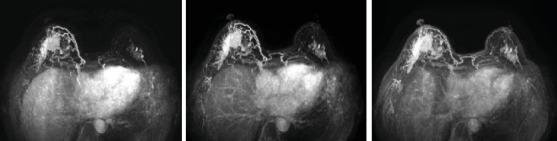

Abstract Image